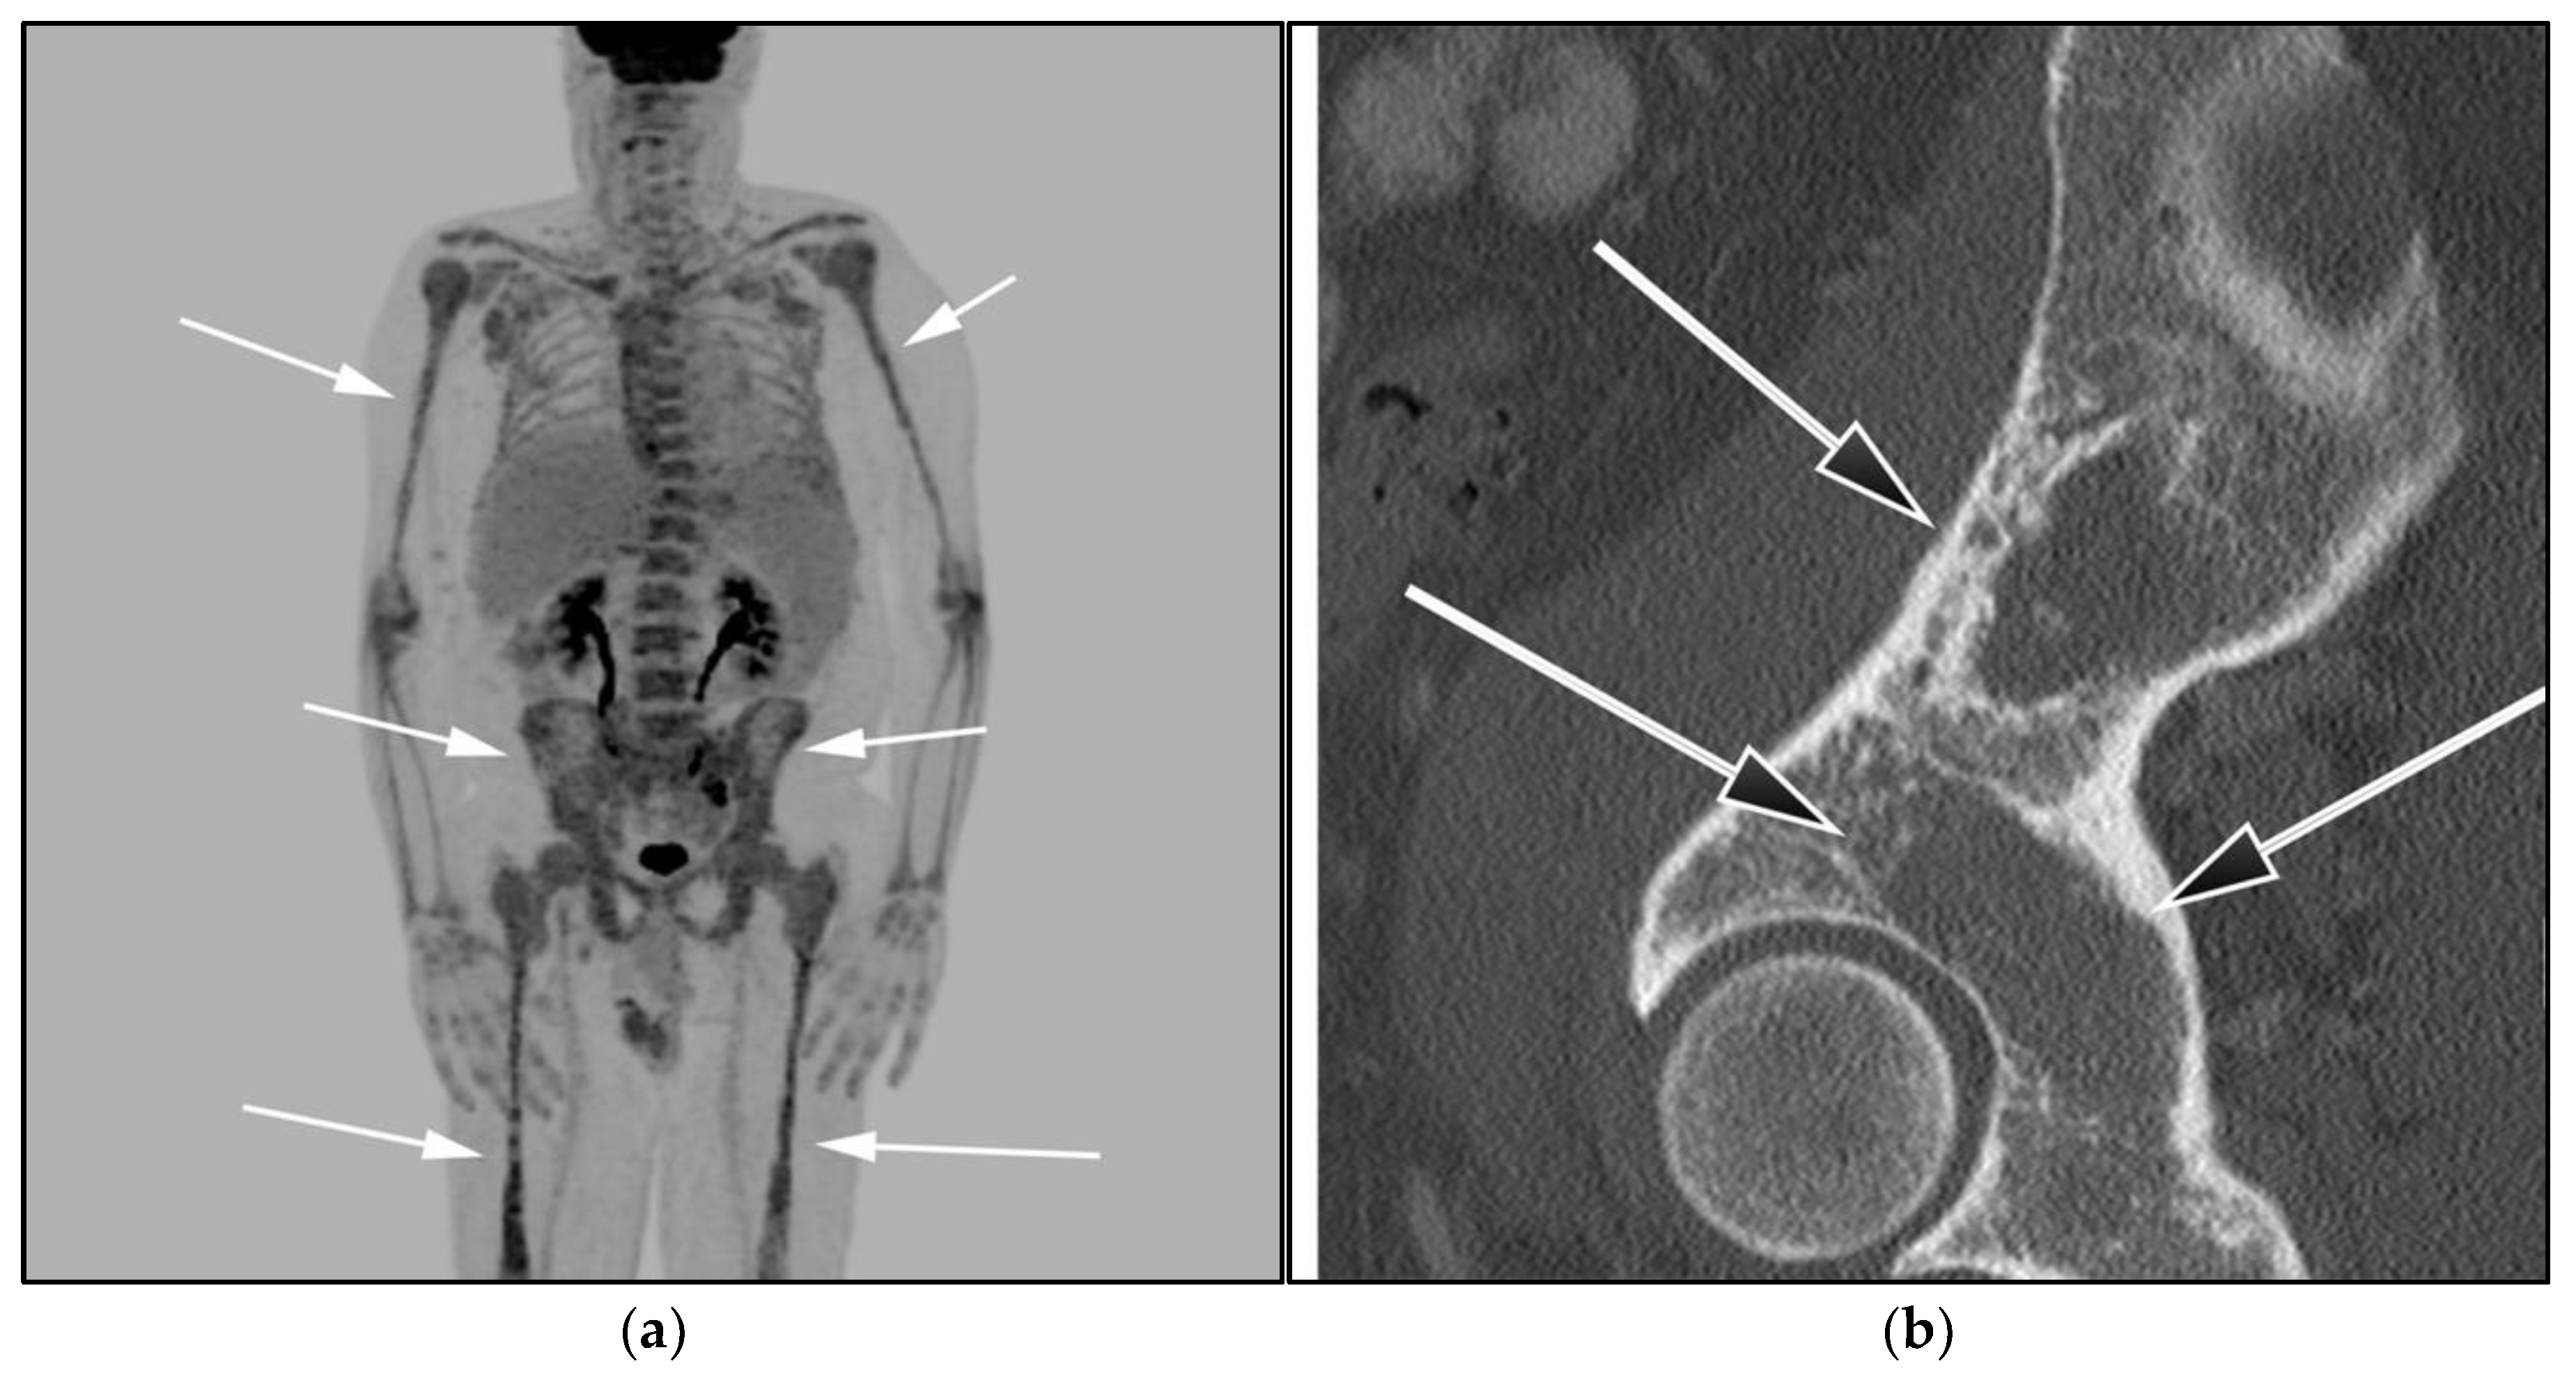

Figure 11.

A 85-year-old-male with known diagnosis of lymphoplasmacytic lymphoma (LPL). (a) Maximal intensity projection (MIP) FDG PET/CT image shows extensive hypermetabolic uptake within the spine, pelvis, and proximal upper and distal appendicular skeleton (white arrows). This patient had not received recent marrow stimulating drugs, which can produce imaging findings consistent with marrow infiltration (b). A sagittal CT image shows diffuse osteopenia, marrow space widening, and no discrete focal lesions (black arrows). This is a very important to differentiate from myeloma, which often presents with frankly lytic lesions.

WM patients can also present with splenomegaly with or without focal lesions and lymphadenopathy typically within the axillary, retroperitoneal, and/or inguinal nodal stations (Figure 12). Cranial nerve deficits can be a manifestation of Bing–Neel syndrome, a rare CNS manifestation seen in WM disease [45,48,52,54]. In Bing–Neel syndrome, neurological symptoms can be directly related to infiltration by lymphoplasmacytic cells or indirectly result from the deposition of circulating IgM immunoglobulin on the brain parenchyma, spinal cord, or cranial or peripheral nerves (Figure 13). Additionally, 18F-FDG PET/CT plays an important role in monitoring therapeutic response after treatment initiation, especially with rituximab. WM patients tend to show elevated IgM levels, known as an IgM flare, which may mimic progressive disease. Imaging plays a pivotal role to differentiate between an IgM flare and true progression, thus obviating the need for repeated marrow biopsy [52]. Imaging may also help in excluding the development of myelodysplastic syndromes, acute leukemia, or DLBCL transformation [52].

Figure 12.

Lymphoplasmacytic lymphoma. (a) Axial FDG PET/CT in the same patient as Figure 8 shows hypermetabolic adenopathy within the bilateral iliac chain (white arrows). (b) Sagittal MRI T1-weighted image in the same patient shows a diffuse variegated appearance of the marrow consistent with marrow infiltration as that seen in multiple myeloma but without definite focal lytic lesions. Lymphoplasmacytic lymphoma combines features of both malignant lymphoma and multiple myeloma.